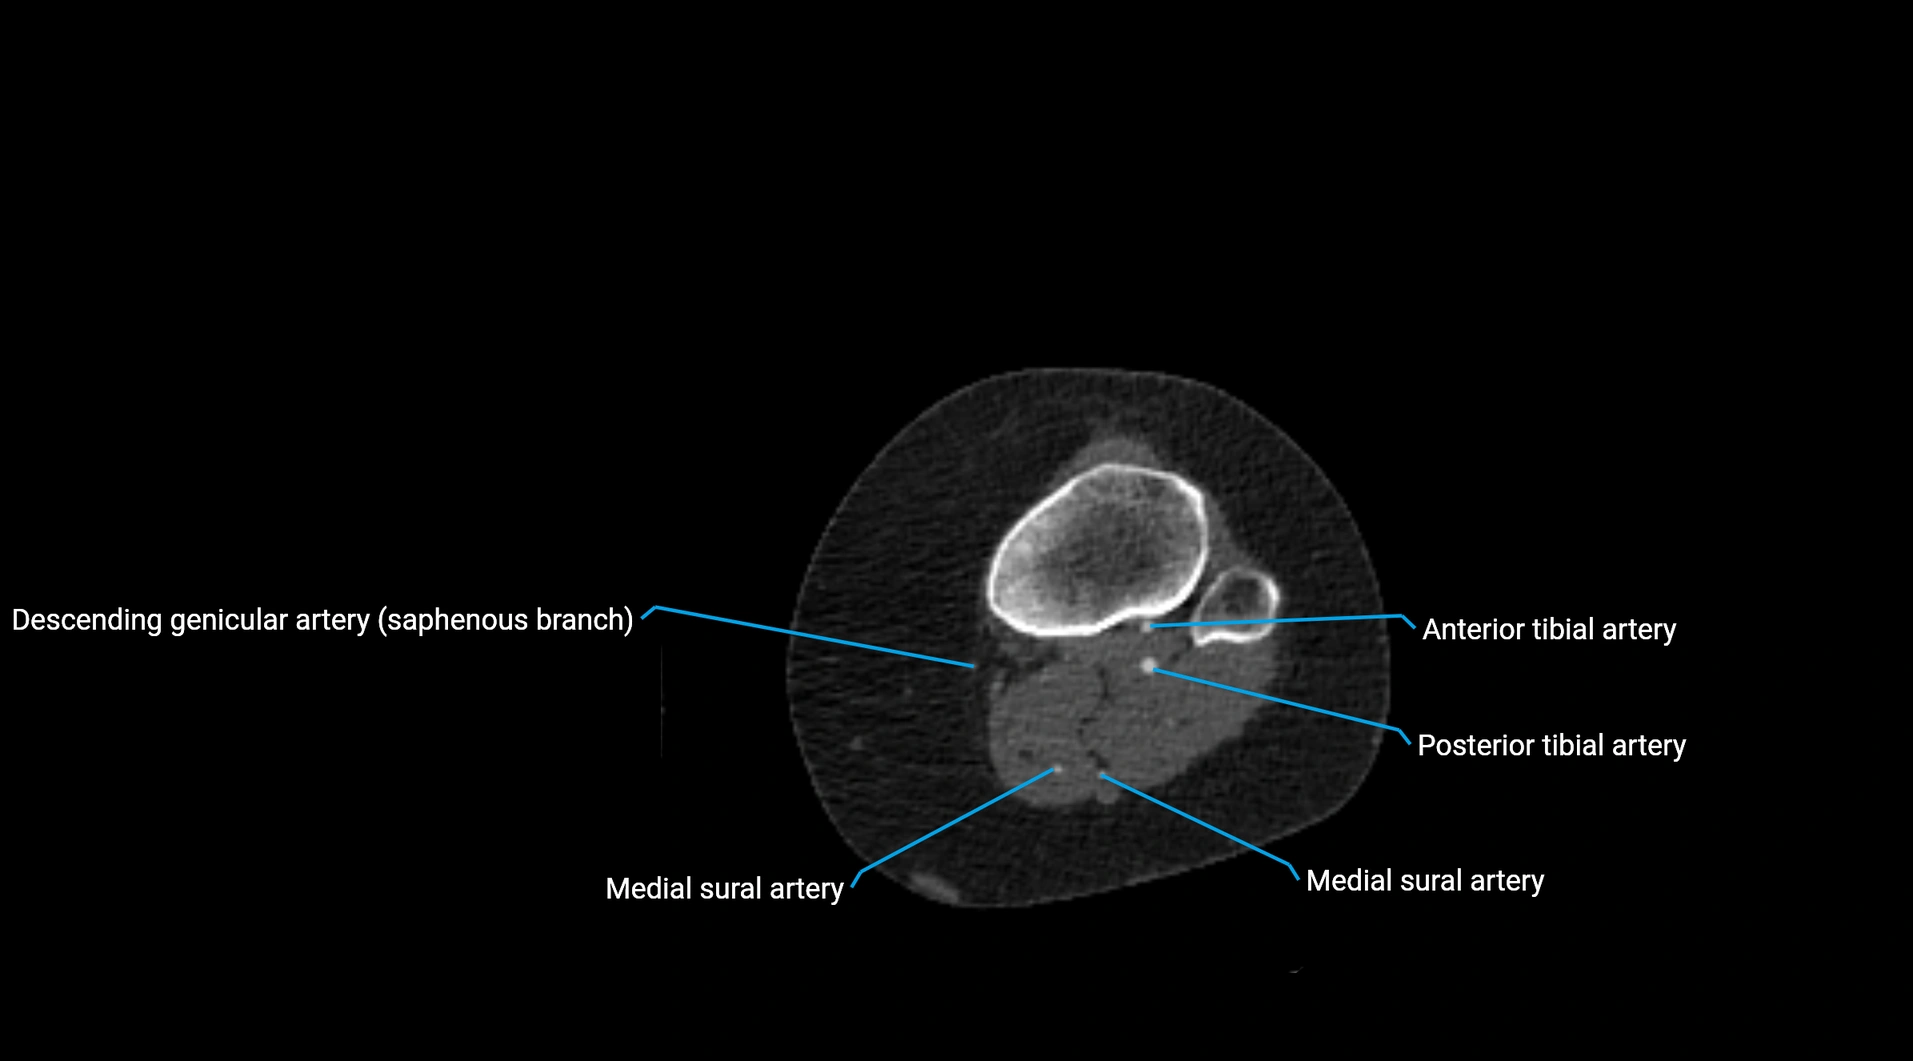

Contrast-enhanced CT (CTA):

• Gold standard for abdominal aortic imaging

• Provides excellent detail of lumen, wall, aneurysm, thrombus, and branch vessels

• Multiplanar and 3D reconstructions help in aneurysm measurement, stent graft planning, and dissection evaluation